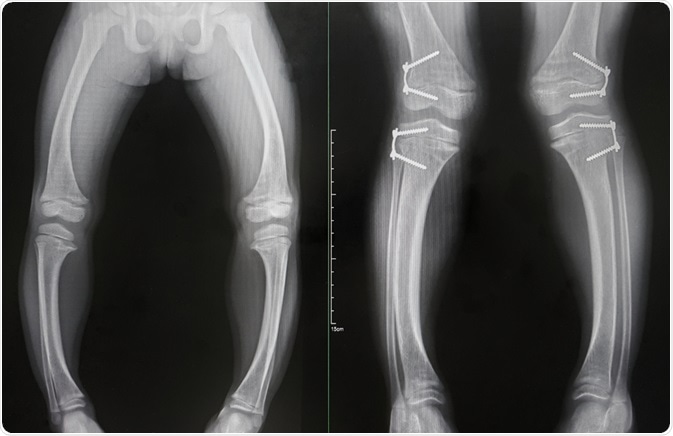

Surgical treatments are generally indicated for severe extremity deformities due to impaired bone growth and fractures due to bone fragility in patients with rickets. Corrective osteotomy and fixation with external fixators, intramedullary nails, Kirshner's wires, plates and casting (including epiphysiodesis) is performed in such cases.